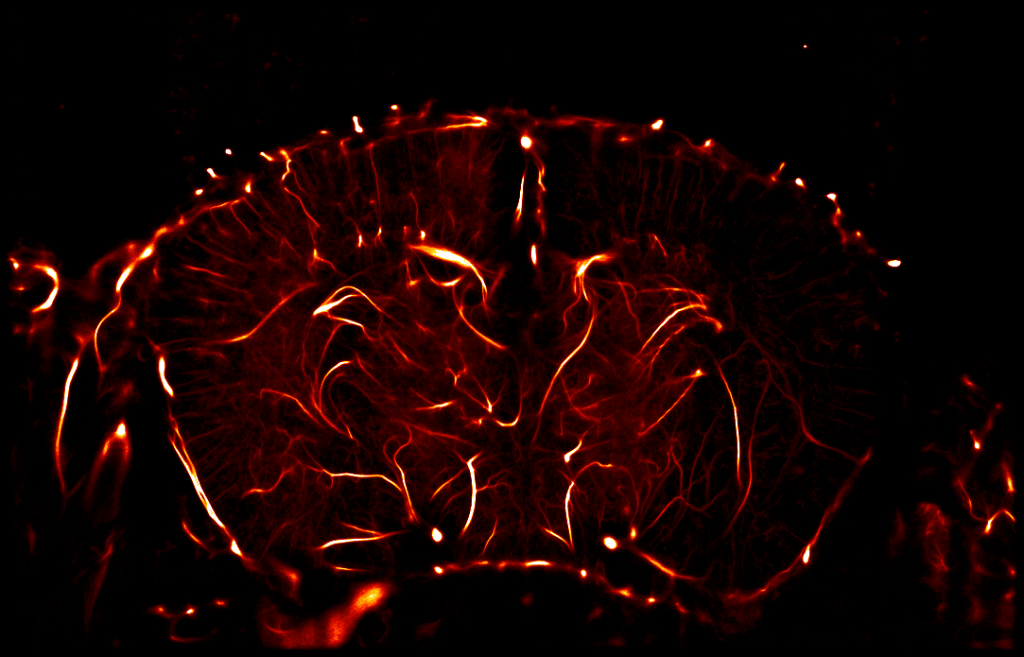

The efficacy of your molecules can be assessed using a set of complementary and multi‑scale approaches: anatomical and molecular medical imaging, neurofunctional imaging, behavioral monitoring, immunohistochemical analyzes, and molecular biology. Every parameter of the study design – administration route, timing, therapeutic regimen, readouts, group size, and inclusion of reference compounds – is customizable and carefully harmonized to meet your specific needs.

Immunohistochemistry, Immunofluorescence, and Histology